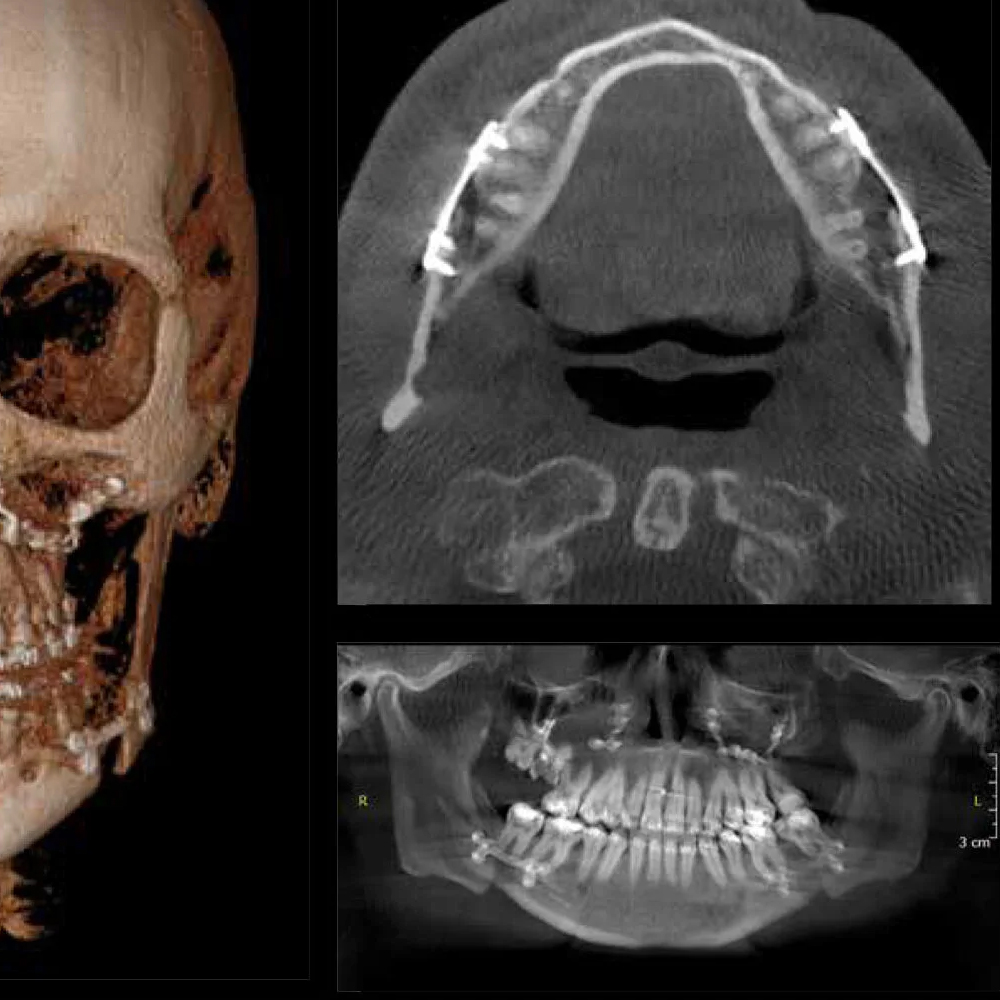

Volümetrik Tomografi (CBCT), alt ve üst çene ile dişlerin üç boyutlu olarak incelenmesini sağlayan ileri bir röntgen yöntemidir. Geleneksel 2D röntgenlerin aksine, CBCT ile diş, çene kemiği ve çevresindeki anatomik yapı detaylı olarak görüntülenir. Bu yöntem özellikle implant planlaması, gömülü diş analizi ve ortodontik değerlendirmelerde tercih edilir.

EGE-RAD’da kullanılan modern CBCT cihazları, düşük radyasyon dozu ile yüksek çözünürlüklü volumetrik görüntüler sunar. Alt ve üst çene kemik yoğunluğu, sinüs boşlukları, diş kökleri ve mandibula/ maksilla anatomisi ayrıntılı olarak değerlendirilir.

Üç boyutlu analiz: Kemik yoğunluğu, sinüsler, diş kökleri ve mandibula/maksilla anatomisi net görülür.